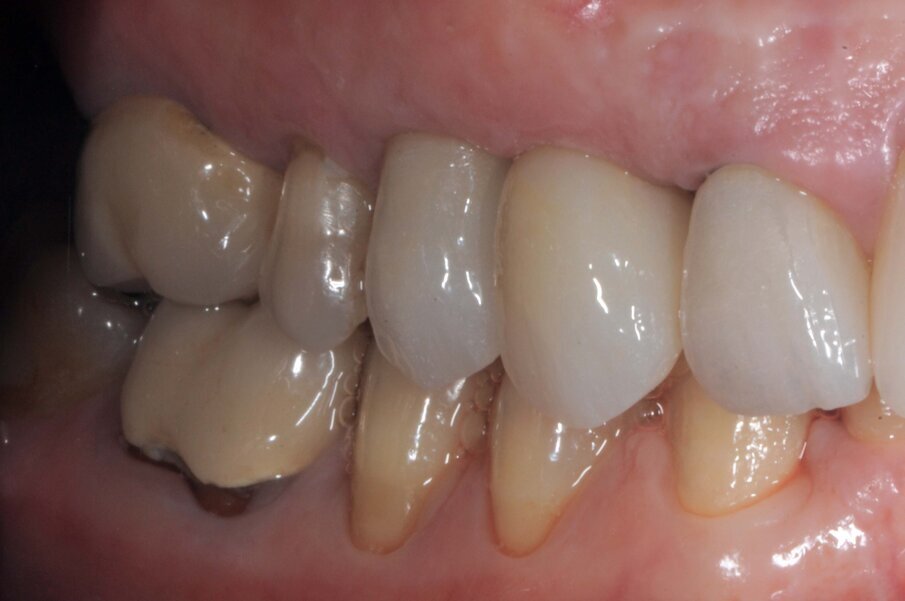

Le corone sui denti 1.3 e 1.4 furono rimosse, il dente 1.3 fu estratto e l’alveolo fu riempito con una membrana di PRGF ottenuta tramite centrifugazione del sangue della paziente con il sistema Endoret e un provvisorio fu consegnato sui denti 1.3 e 1.4 (Fig. 5, 6). Dopo otto settimane fu eseguita una nuova cone-beam e la chirurgia fu pianificata (Fig. 7). Si eseguì un lembo a tutto spessore, fu eseguita l’osteotomia e fu inserito un impianto BTI Core 3.5 × 8.5. Un pilastro Unit fu avvitato e un tappo di guarigione fu applicato. L’osso ottenuto dalla fresatura mescolato con una membrana di PRGF fu applicato sul lato palatale per compensare una piccola deiscenza, una seconda membrana fu applicata sopra l’osso circostante e un innesto di tessuto connettivo prelevato dalla tuberosità fu suturato vestibolarmente per ricreare la bozza canina. Punti di sutura staccati furono eseguiti con un filo in PTFE (Figg. 8-11). Dopo quattro mesi il provvisorio fu rimosso e i tessuti apparivano sani e con un buon spessore di tessuto connettivo vestibolare per garantire la stabilità nel tempo del risultato. Fu eseguita un’impronta con la tecnica del cucchiaio aperto e dopo due settimane furono consegnate una corona in zirconio cementata sul dente 14 ed una avvitata sul denta 1.3. Il profilo di emergenza della corona sull’impianto appariva ideale. Purtroppo, a causa della mancanza del picco osseo sul versante distale del dente 1.2, non si ottenne una papilla di altezza adeguata. Ciononostante la paziente si disse soddisfatta del risultato e rifiutò ulteriori terapie per correggere il difetto residuo (Figg. 12-15).